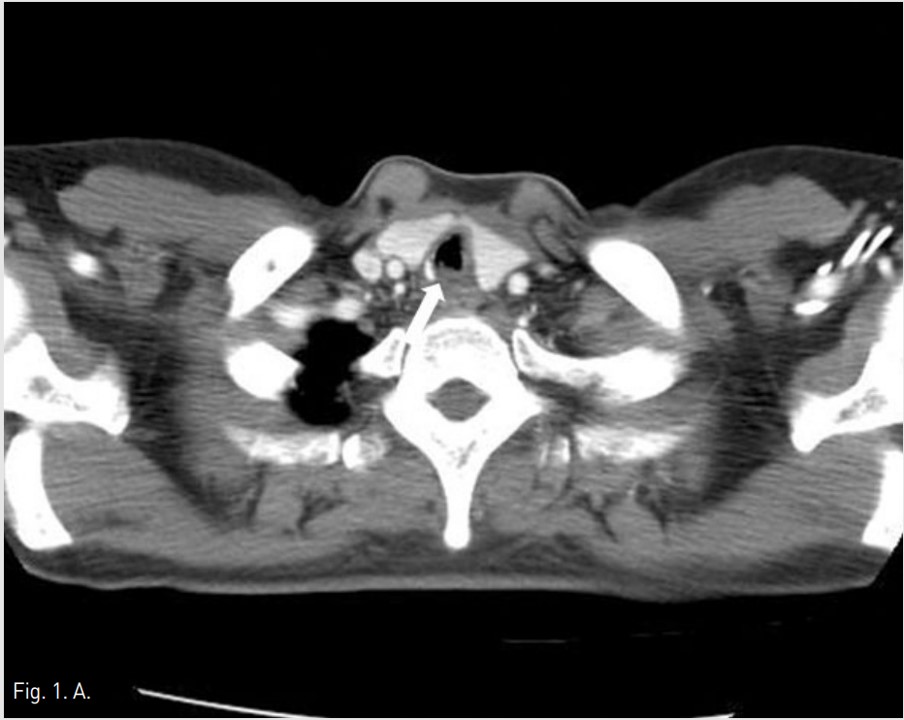

Fig. 1. A

Fig. 1A-1B Axial chest CT image (A) shows tracheal stenosis(Arrow in A) at thyroid gland level. Coronal chest CT image (B) shows multifocal irregular luminal narrowing (Open arrows in B) of upper trachea from C6 to T1 level.